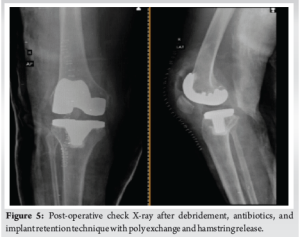

At the 3-month follow-up, the patient exhibited walking difficulties with a 10° FFD in the left knee and a urinary tract infection (UTI). She was hospitalized for supervised physiotherapy and received intravenous antibiotics. The patient was discharged after satisfactory training. Eight months post-surgery, the patient arrived at the emergency department with swelling in the right knee and FFD in both knees, which had persisted for 2 days. While the patient couldn’t recall any traumatic incident, her attendant suggested a possible bathroom slip. Radiographic examination revealed a posterior knee dislocation in the right knee (Fig 4). The medical team promptly reduced the dislocation under sedation in the operating room, using fluoroscopy guidance. Knee aspiration, performed under aseptic conditions, revealed liquefied hematoma, indicating a chronic condition. The knee was immobilized in a posterior slab. Periprosthetic infection tests were negative, and the neurological examination was inconclusive due to whole-body stiffness, hypertonia, and an uncooperative patient. The knee remained unstable, attributed to significant hamstring hypertonia. During reoperation, the surgical team observed collateral ligament laxity and hamstring tightness without signs of infection. They performed a pulse lavage wash, extensive hamstring release, and replaced the poly insert with a thicker 17 mm, following the debridement, antibiotics, and implant retention technique (Fig. 5). The infection work up did not yield any result. The left knee was manipulated and fitted with a brace to address FFD. The post-operative period was uneventful, with suture removal on the 12th day and proper wound healing. The right knee was immobilized in a brace for 6 weeks, while the left knee began mobilization with continuous passive motion and night time bracing. Physical therapy was initiated, but the patient remained uncooperative, with persistent whole-body hypertonia and reluctance to leave the bed. The patient was discharged with appropriate instructions.